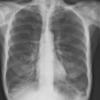

COPD

Date: 06/06/2004

Views: 14534